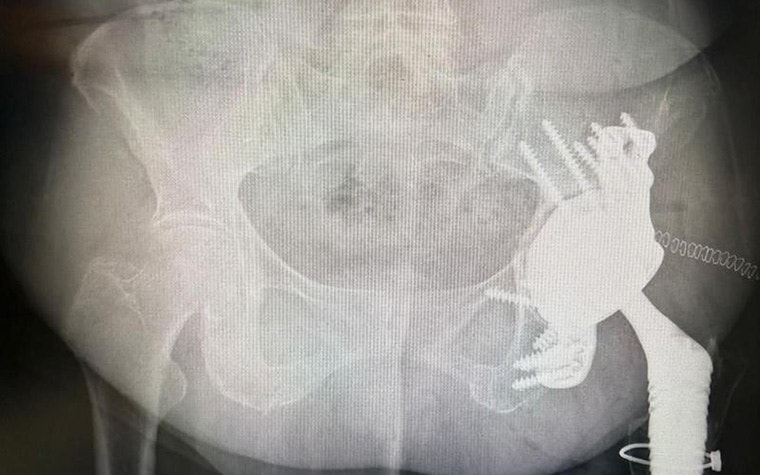

A few years ago, she suffered a periprosthetic fracture of the femur caused by polyethylene wear. Dr. Van Overschelde performed revision surgery with a REEF prosthesis on the femoral side and an acetabular revision with a revision cup and augment.

Then, six months ago, the patient began experiencing ongoing groin pain and difficulty walking after a fall. A CT scan revealed another periprosthetic acetabular fracture with a complete dissociation of the pelvis. The fracture was severe enough that natural healing was, unfortunately, not occurring.

Beyond these complications, the patient also had severe osteoporosis and a history of pseudo-tumor development, resulting in significant bone destruction. It was no straightforward case for Dr. Van Overschelde, and he had to navigate many complexities to restore function and minimize the risk of future medical interventions.

The aMace implant helps surgeons break the revision cycle. It is designed for minimal risk of dislocation, is based on unique 3D pelvis analyses to quantify bone loss and available bone stock, and makes long-term fixation possible with crossed screw trajectories and a defect-filling porous augment.

For this particular case, the team included an important modification to the implant design based on these insights: a polished surface on the anterior side to avoid irritating the surrounding soft tissue.